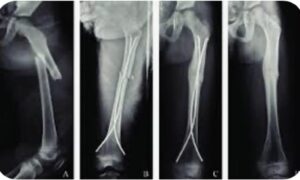

وأشار الدكتور صبري زيادة إلى أن علاج كسور الأطفال يعتمد على نوع الكسر ودرجة الإزاحة:

1.العلاج الغير جراحي

الكسور المستقرة وبدون إزاحة تعالج بوضع جبيرة أو جبس على الطرف المصاب.

وبالنسبة للكسور المائلة أو المزاحة،وتحتاج رد الكسر دون جراحة،وهذا الإجراء يسمى رد مغلق (Closed reduction).

2.العلاج الجراحي في بعض الحالات يلزم إجراء جراحة لمحاذاة قطع العظام وتثبيتها بالأسلاك أو الصفائحُ والمسامير المعدنية،حيث قد يوصي طبيبك بإجراء جراحة إذا:اخترق العظم الجلد وهذا النوع من الإصابات يسمى الكسر المفتوح وهو معرض لخطر الإصابة بالعدوى ويتطلب علاجًا محددًا.